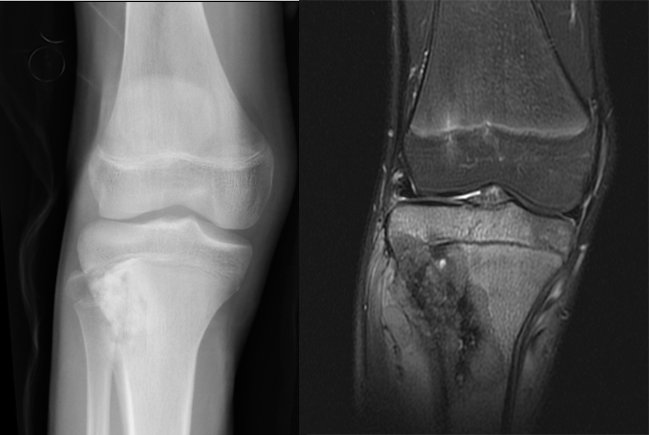

反应性骨增生是病变周围正常骨组织遭到肿瘤破坏后的反应骨,它并非骨肿瘤的特有征象,在骨创伤、骨感染时也可见到。良性肿瘤如骨样骨瘤、骨母细胞瘤等周围可见反应性骨增生(图 51、图 52)。原发于骨髓的恶性肿瘤如尤因肉瘤、骨淋巴瘤、骨恶性纤维组织细胞瘤等以及部分骨转移瘤均可在肿瘤周围产生大量反应性骨增生(图 53、图 54)。X 线平片或 CT 表现为松质骨内斑片状均匀骨化影或大量棉团样骨化影。亦有在多发灶性溶骨性破坏周围产生散在片状骨化影。

图 53.反应性骨增生:骨淋巴瘤

图 54.反应性骨增生:骨转移瘤